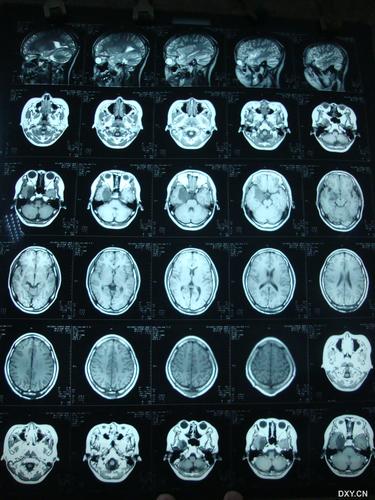

相信有些人在生活中一定看到过癫痫患者,癫痫患者不管是精神方面还是身体方面都会受到别异常的痛苦,这是很多人都不想看到的一种结果。那么,六七个月癜痫的早期症状有哪些呢?